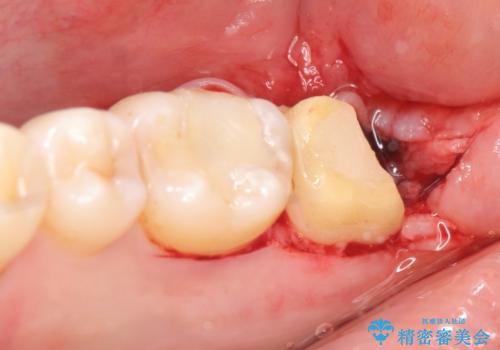

銀歯を除去し、歯周外科処置(右下7遠心の骨整形及びディスタルウェッジ)を行った後にメタルボンドクラウンによる補綴を行いました。

歯周外科処置(右下7遠心の骨整形及びディスタルウェッジ)により、深部に及ぶう蝕を除去するとともに歯肉縁上の健全歯質を獲得でき、適合の良い被せ物を作製することができました。